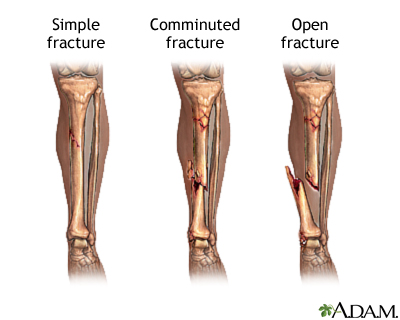

Fractures of the bones are classified in a number of ways. A simple fracture involves a single fracture line through a bone. A comminuted fracture is one in which the bone has been fractured into two or more fragments. An open fracture is one in which the fractured bone penetrates the skin.